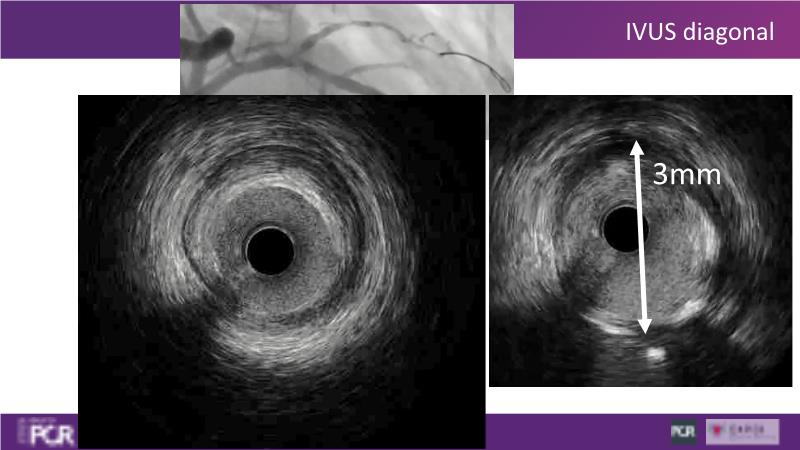

Through the study of two cases, this session examines the need for stenting bifurcation lesions and the role of DEB technology in avoiding stent-related complications in long diffuse disease. It emphasizes the benefits of SELUTION SLR balloons for de novo lesions, discussing how sustained limus release technology can broaden DEB indications and reduce metal usage, understanding the limitations of DES and the emerging role of DEB with sustained limus release, and learning how to identify dissections that can be left unstented.